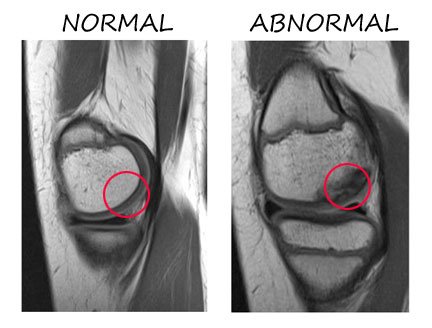

If you look at the two MRI scans on the right, it may not be altogether easy for you to interpret, but the slices are through the rounded condyle of the femur, with the normal knee on the left and the affected knee on the right. Looking inside the red circles one can see on the left that the bone (whitish) and layer of overlying joint cartilage (greyish) are both smooth and intact. In the red circles on the right, however, the bone is not at all healthy and has lost its clear rounded contour, while the overlying cartilage is thinned and boggy-looking, although still intact.